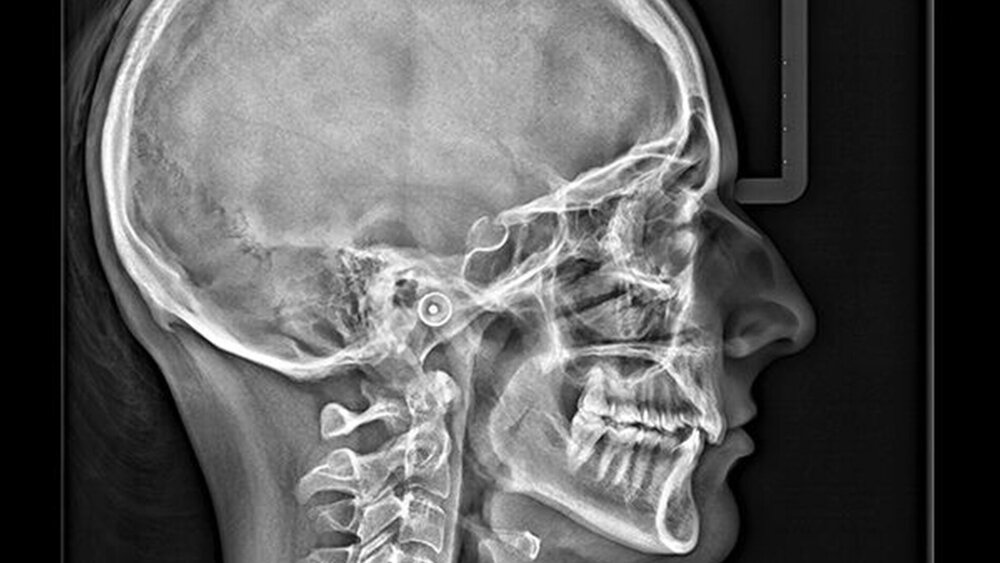

Kieferorthopäden haben zusätzlich die Möglichkeit, den Scan Ceph-Fernröntgen-Arm für herausragende kephalometrische Bildgebung und Scanzeiten wahlweise zu kaufen oder später nachzurüsten. Bei Fernröntgen-Aufnahmen, die mithilfe des Scan Ceph-Arms angefertigt werden, wird mithilfe der Auto Tracing Option – in der Vergangenheit bekannt unter KFO-Modul – in nur zehn Sekunden eine automatisierte Durchzeichnung erstellt. Diese vereinfacht die Diagnostik zusätzlich: Integriert in Carestream Dentals Imaging Software – CS Imaging version 8 – erkennt das KFO-Modul (oder das Auto-Tracing-Modul) automatisch anatomische Strukturen und führt die Durchzeichnung durch. So spart das gesamte Team wertvolle Zeit und erhält schnellere Ergebnisse. Diese Software deckt die gängigsten Analyse-Verfahren ab, wie Ricketts, McNamara, Steiner und Tweed.